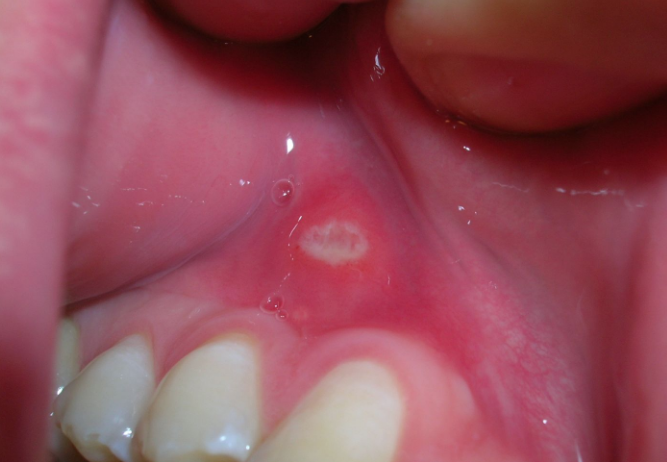

Marmara Üniversitesi'nde Baş ve Boyun Kanserleri Haftası kapsamında gerçekleştirilen etkinlikte uzmanlar, ağız yaralarının kansere yol açtığını belirterek uyarılarda bulundu.

Uzmanlar, boyunda şişlik, uzun süren ses kısıklığı, yutma güçlüğü, inatçı öksürük ve 3 haftadan uzun süre iyileşmeyen yaraların baş ve boyun kanserleri açısından şüphe taşıyabileceğini  belirtti. Prof. Dr. Çağatay Oysu, baş boyun kanserlerinin ağız içi, dil, dudak, bademcik, geniz, sinüs, boğaz, yutak, ses telleri, boyun, tükürük bezleri ve tiroid bezinin içinde olduğu geniş bir alanda yer alan tümörler grubu olduğunu ifade etti.

3 HAFTADAN UZUN İSE...

İnsanların doktora geç başvurması nedeniyle tedaviye geç kalındığını söyleyen Prof. Dr. Oysu, ağız içinde yeni oluşan ve protez diş, sigara ya da rahatsız edici madde maruziyeti gibi etkenler ortadan kalktığı halde üç haftadan uzun iyileşmeyen yaraların varlığında da yine şüphelenmek gerekiyor. Ağız içi kanserler özellikle erken evrede birçok iyi huylu lezyonla karışarak tanısı gecikebiliyor. Bu yüzden hastanın alışkanlıklarının detaylı sorgulanması ve iyileşmeyen lezyonlarda mutlaka biyopsi ile tanı koyulması gerekiyor." şeklinde konuştu.